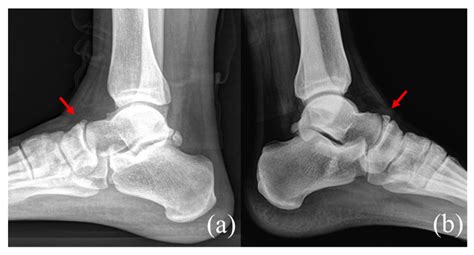

• X-rays: Useful for identifying fractures, bony deformities, or structural issues.

• MRI (Magnetic Resonance Imaging): The gold standard for detecting early stress fractures that may not show up on a standard X-ray.

• CT Scan: Provides detailed images of the bone structure if a complex fracture is suspected.